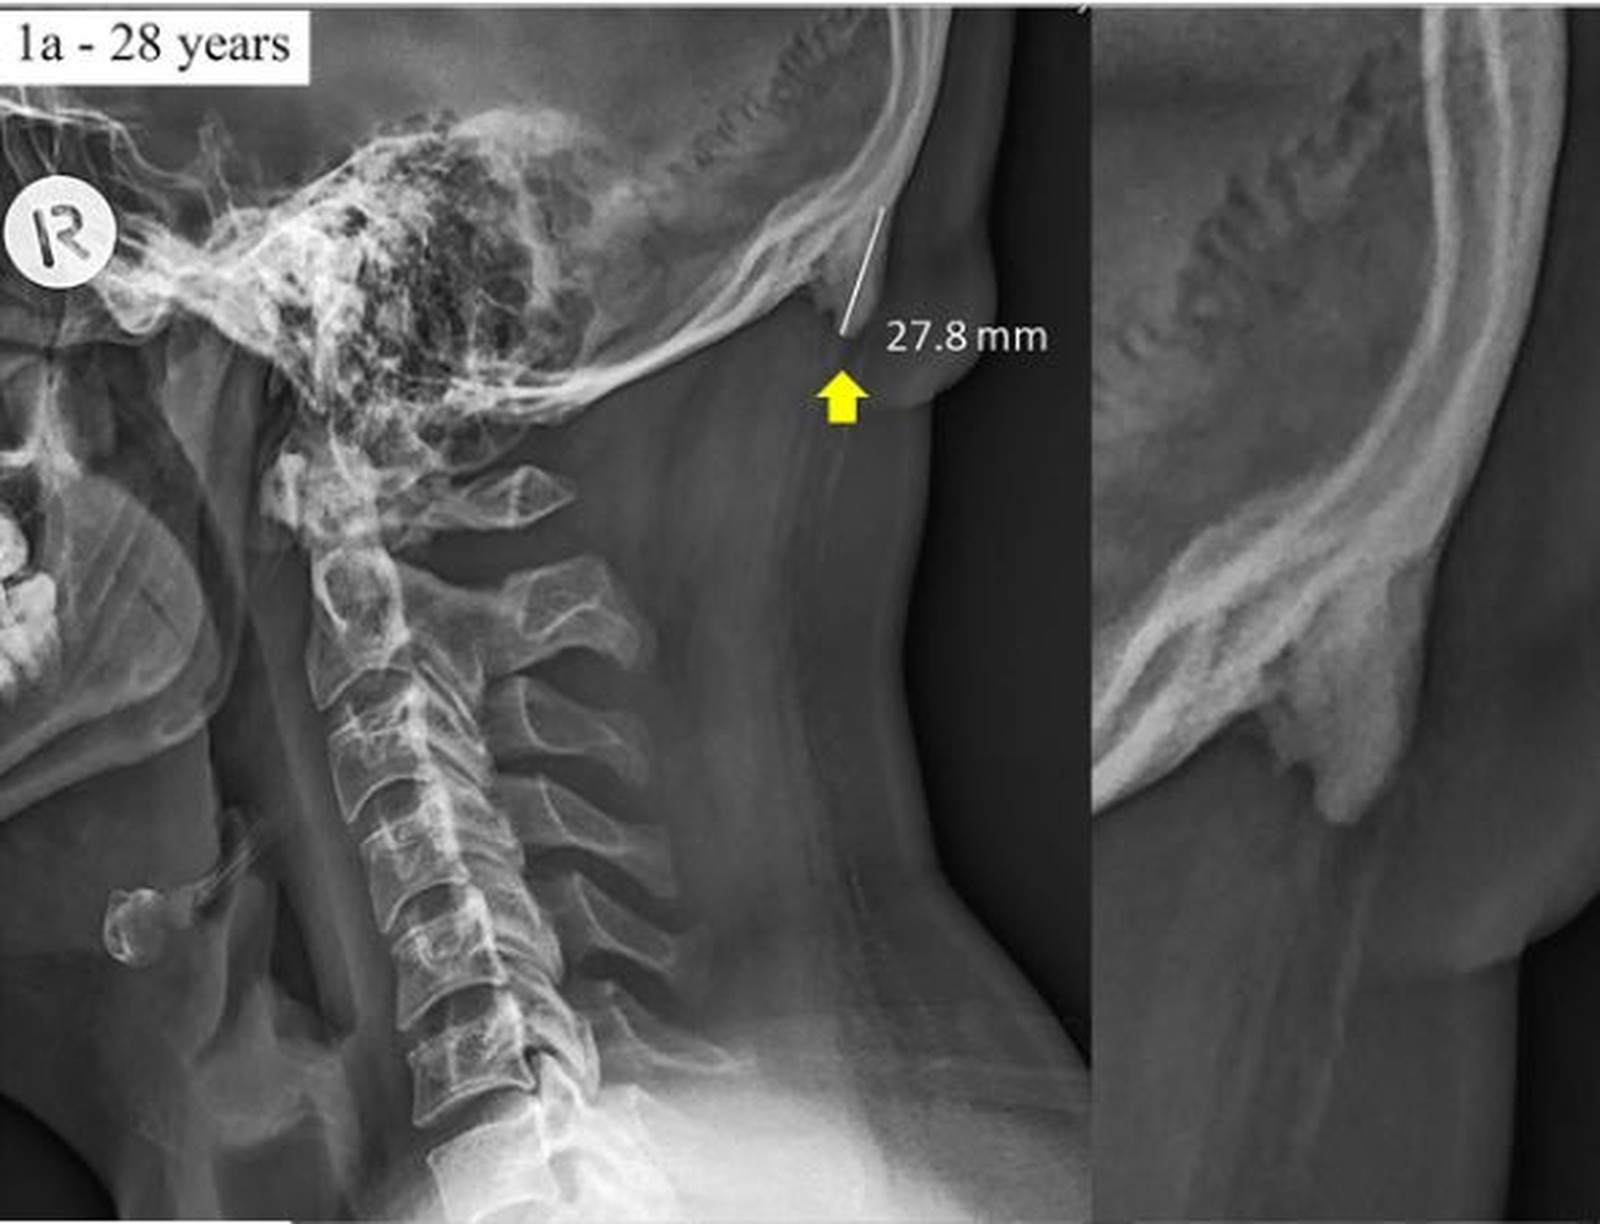

smartphonesDe acordo com a pesquisa, a posição adotada para utilizar smartphones causa uma protuberância na parte de trás do crânio (foto ao lado). A posição em questão é a cabeça abaixada, com o pescoço dobrado para baixo, comum a quem olha a tela do smartphone.

Essa irregularidade é uma espécie de calo e se posiciona na junção entre pescoço e crânio. A deformidade ficou conhecida entre os australianos como “os chifres dos jovens”.